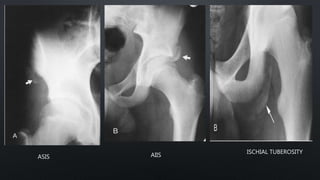

ASIS AIIS

ISCHIAL TUBEROSITY